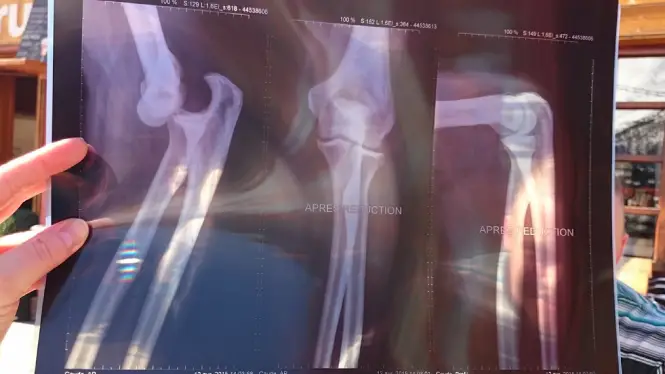

Don’t break yourself

A season isn’t a one-week holiday. You’re here for months. Pace yourself. You’ll ride better by the end of the winter than at the start, so leave the big “send it” days for later.

Don’t wing it, get proper cover

We all hope the worst won’t happen, but you’ll be riding a lot. The risk of injury increases simply because you’re out so often. Rescue and treatment costs mount up fast if you’re uninsured.

If you want the deeper explanation, read why ski insurance matters. If you’re doing a season, go straight here for the best ski season insurance.